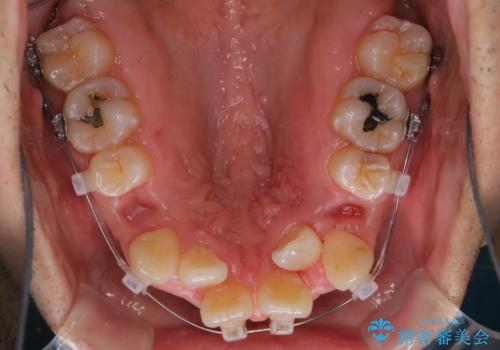

- ワイヤー装置で矯正中の方です。歯磨きがしずらく、専門的な機械でクリーニングしてほしいとの事でした。PMTC60分コースを行いました。

ワイヤー矯正中はブラッシングが難しくなるため、磨き残しが多くなることがあります。適切な道具を使って、適切なブラッシング方法を習得することで、磨き残しを減らすことができます。

また、矯正で歯の移動があると今までなかったところに隙間が出てきたり、ガタつきが解消されてきたりすることで、お口の中の環境が変わります。

矯正治療中も清潔な口腔内を保つことは、とても大切です。そのため、定期的に専門的な機械・材料を使用したProfessinnalcleaning(pmtc)を行うことがおススメです。